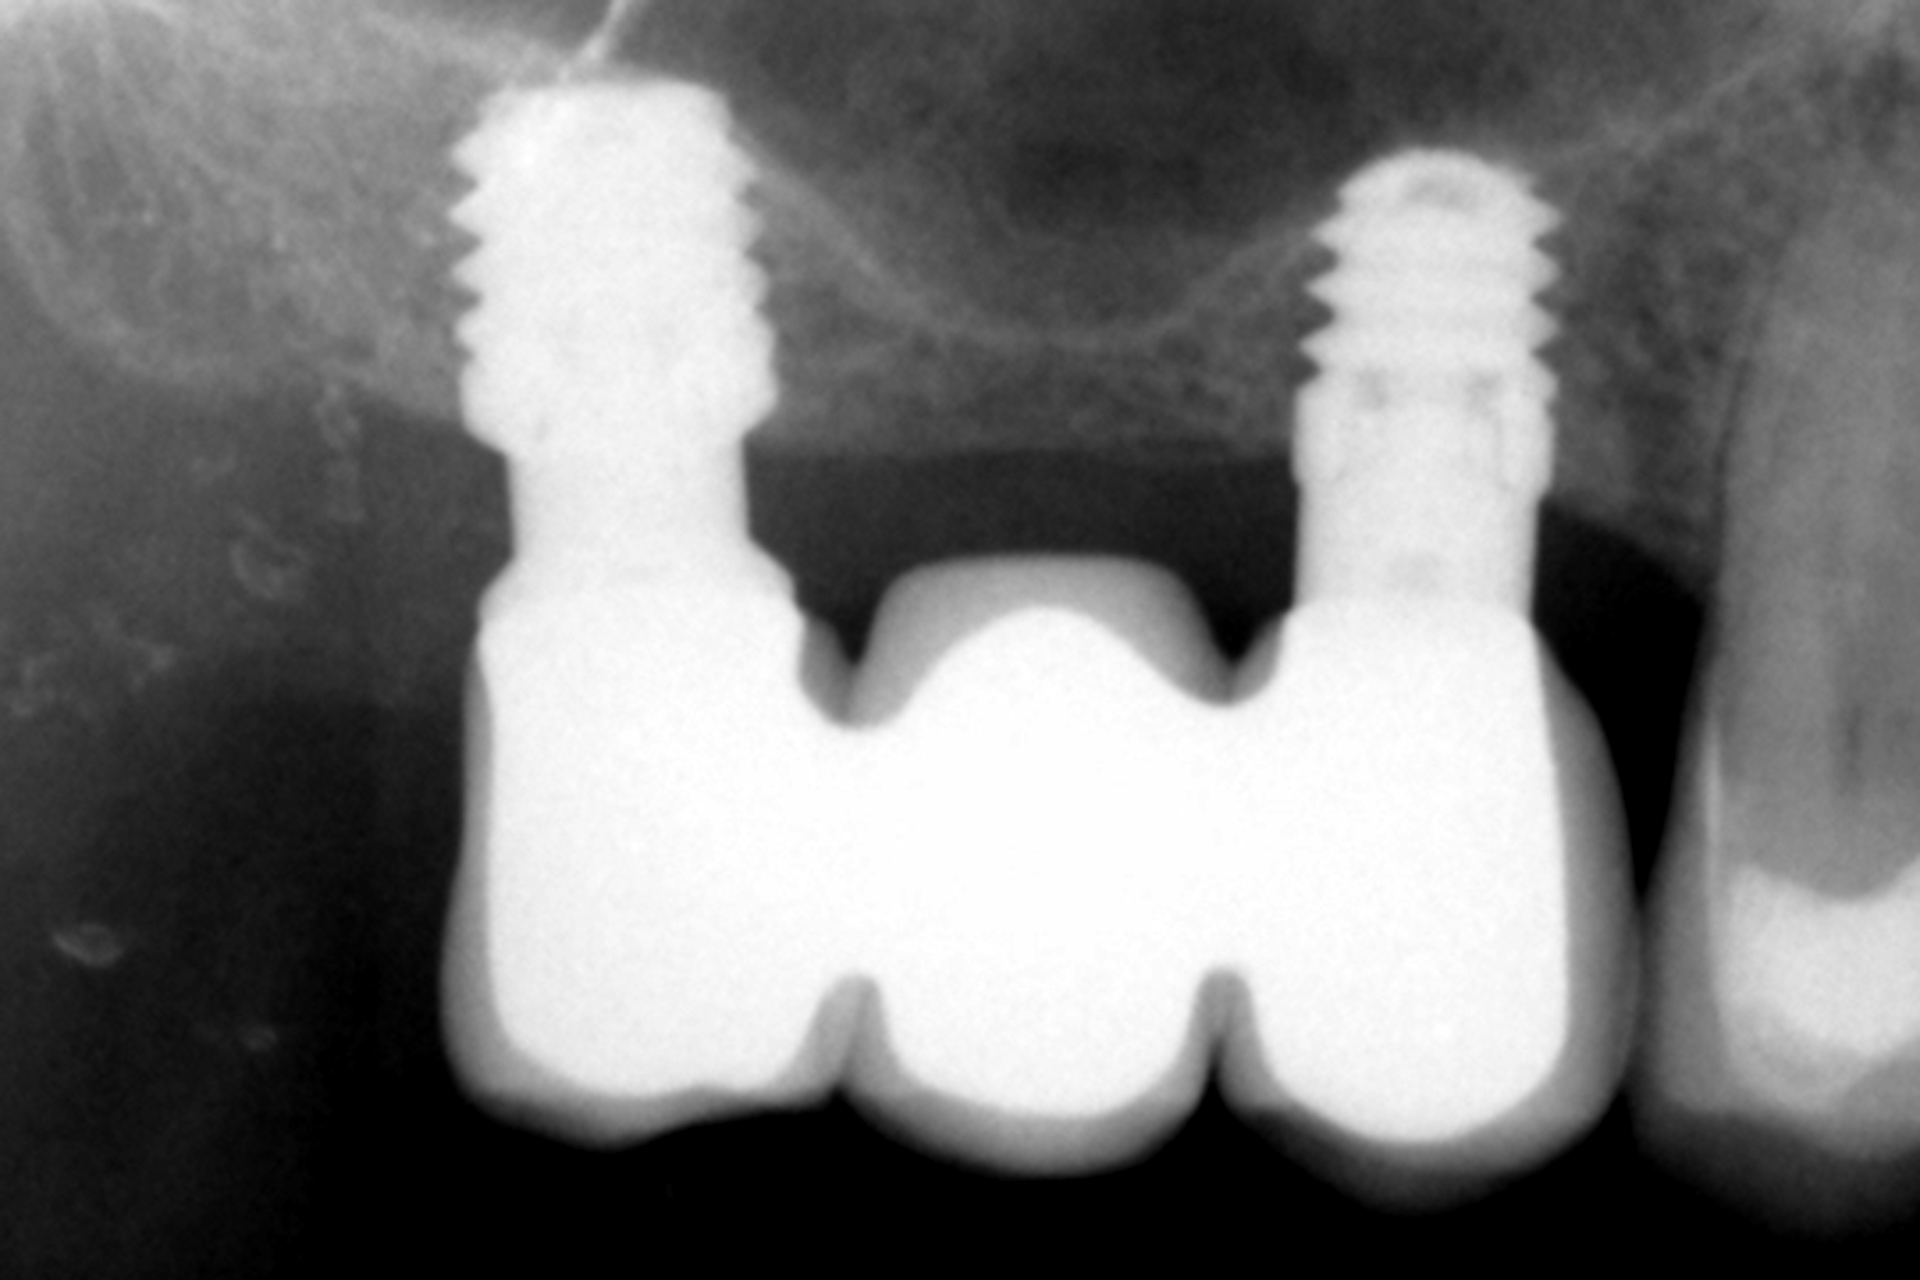

Tutti gli impianti sono stati caricati entro 24 ore dall’inserimento mediante protesi provvisorie in resina a carico immediato, realizzate con strutture a barra articolata. L’analisi dei diversi tipi di protesi ferulizzate ha evidenziato una predominanza delle riabilitazioni parziali. Il gruppo più numeroso era costituito dalle protesi supportate da due impianti e due elementi dentari, pari al 33,3% dei casi, seguito dalle protesi complete, presenti nel 19,4% dei pazienti. Altri disegni protesici sono stati utilizzati con frequenze comprese tra l’8,3% e il 16,7%, riflettendo l’adattamento del piano terapeutico alle specifiche condizioni anatomiche di ciascun paziente, mantenendo in tutti i casi la ferulizzazione rigida degli impianti come principio biomeccanico fondamentale (Figura 1).

In 19 impianti sono state eseguite procedure complementari contestualmente all’inserimento implantare: in due casi rigenerazione verticale con osso autologo da fresaggio associato a PRGF-Endoret; in 11 casi rialzo del seno mascellare transalveolare con osso autologo e PRGF-Endoret; in sei casi sovracorrezione vestibolare mediante osso autologo e PRGF-Endoret, associando uno strato di biomateriale (idrossiapatite bovina) per ridurre il riassorbimento volumetrico. Quattro impianti da 4,5 mm sono stati ferulizzati ad altri impianti della stessa lunghezza, per un totale di otto impianti ultra-corti ferulizzati tra loro, configurando ponti supportati da tre impianti. La protesizzazione definitiva è stata eseguita tra tre e nove mesi dopo il carico immediato. Le protesi definitive erano in metallo-ceramica nell’80,6% dei casi e in resina con struttura metallica nei restanti.

Durante il periodo di osservazione non è stato registrato alcun fallimento implantare, con una sopravvivenza del 100%. Non sono state riportate complicanze chirurgiche e sono state osservate solo quattro complicanze protesiche, tutte rappresentate da allentamento delle viti nella fase di protesi definitiva; pertanto, anche la sopravvivenza protesica è risultata del 100%. Il follow-up medio è stato di 38,5 ± 3,60 mesi, con un intervallo compreso tra 12 e 60,5 mesi.

Al termine del follow-up, la perdita ossea crestale media è stata di 0,73 ± 0,18 mm in mesiale e di 0,85 ± 0,34 mm in distale. Alcuni casi clinici rappresentativi sono illustrati nelle Figure 2-10.